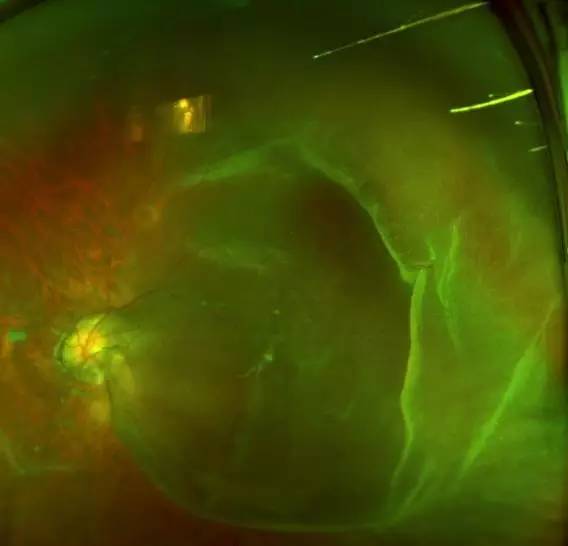

二天,赶上周末,家人陪着肖先生连忙赶到深圳易游体育进行诊治。经过一系列检查,确诊肖先生为超高度近视裂孔性视网膜脱离,由于黄斑区视网膜全部脱离,必须要尽快做手术。

肖先生左眼术前眼底照相图

当日下午,赵铁英院长便为肖先生进行了急诊视网膜脱离手术。因为肖先生是 少数的超高度近视,比正常人的眼球直径扩张很多,眼球壁相当薄,且视网膜脱离颇为严重。赵院长选择何种手术方式都有其困难所在,视网膜薄、球壁也薄,无论是内路手术还是外路手术都非常艰难、各有利弊,所以赵院长在术前选择手术方式的时候,就要争取较大可能尽量避开各种不利因素,取得较大 。

赵院长在后来查房时讲到,类似这种超高度近视视网膜脱离的患者,因其视网膜和球壁非常薄弱,玻璃体结构异常,医治起来便非常困难, 率低,且复发率高,所以在选择手术方式时,要充分考虑患者的病情, 衡各种手术方式的利弊。